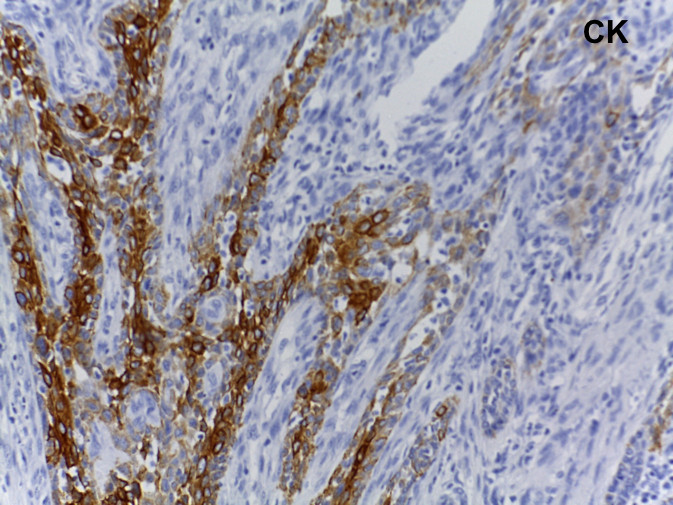

Mujer de 61 años con padecimiento de 1 año de evolución caracterizado por tumor en cuello, disfonía y disfagia progresiva.

Se le realizó tiroidectomía total y laringectomía.

Tumor de células fusiformes con diferenciación semejante a timo (SETTLE por sus siglas en inglés).